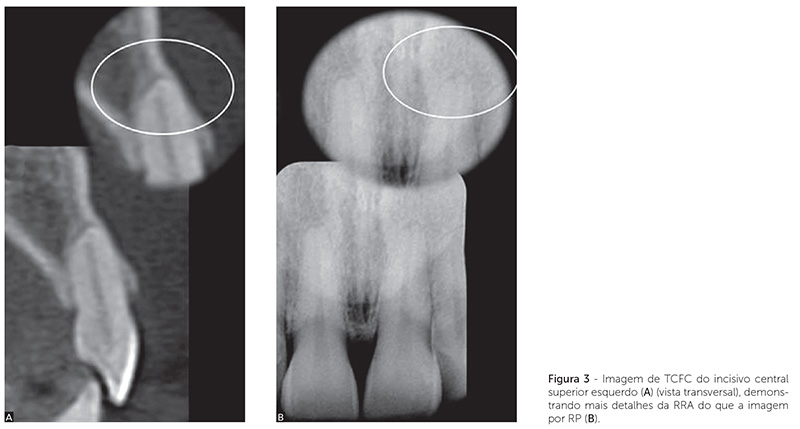

A Figura 2 mostra radiografias periapicais de um incisivo lateral maxilar, em que a RRA não alterou após a finalização do movimento ortodôntico em longo prazo. A Figura 3 mostra a diferença de detalhes de uma RRA em um incisivo central, por meio de TCFC e RP. A Figura 4 mostra a sobreposição de imagens, sugerindo RRA por meio de RP, enquanto a imagem de TCFC mostra ausência de RRA.

Evidenciou-se RRA em incisivo lateral superior sem alteração em longo prazo (Fig. 2); presença de RRA em incisivo central (Fig. 3) e ausência de RRA (Fig. 4) em pré-molar (superior), por meio de RP e de TCFC.

Esses resultados sugerem que as RPs, em função de limitações, tendem a superestimar as RRAs nos grupos dentários posteriores (Fig. 3, 4). Esses dados podem ser explicados em vista da presente análise ter sido para todos os grupos dentários. O grupo de dentes, as variações morfológicas apicais, a densidade do osso circundante (cortical óssea), a angulação dos raios, o contraste radiográfico e a sobreposição de estruturas anatômicas podem influenciar as interpretações radiográficas26. Na análise das imagens tomográficas, foi utilizada uma estratégia de navegação com intuito de verificar em todos os planos, o ápice das raízes, com recursos semelhantes aos sugeridos em recente estudo27. Essa estratégia favorece o perfeito manejo de imagens de TCFC, que podem revelar normalidades ou anormalidades incapazes de ser detectadas na RP convencional.